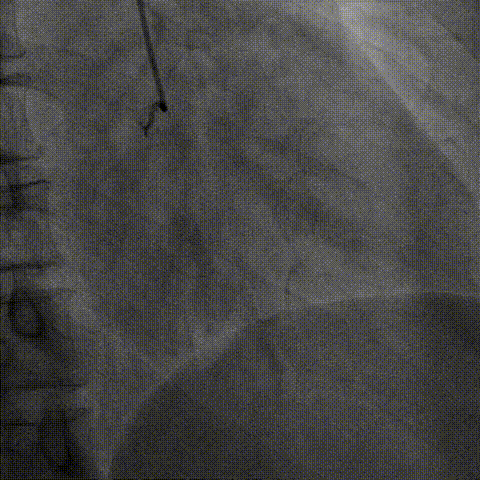

逆向器械:

1、选择近段粗大间隔支;Finecross(150cm);Sion导丝surfing通过侧枝循环至右冠远段,跟进微导管后尝试UB3、Gaia3导丝至闭塞段远段与正向导丝重叠,但闭塞段钙化可能导丝逆向导丝无法进一步前进突破。

策略转换:

1、逆向导丝无法进一步前进突破后及时转换策略,决定以逆向导丝为路标,操控正向导丝定向穿刺逆向导丝。

2、正向升级为Gaia3导丝多投照体位穿刺并靠近逆向导丝,但无法进入远端真腔,升级为Pilot200导丝试图尽量考虑血管真腔加强支撑力后启动Reverse-Cart,多体位操控后导丝幸运进入血管远端真腔。